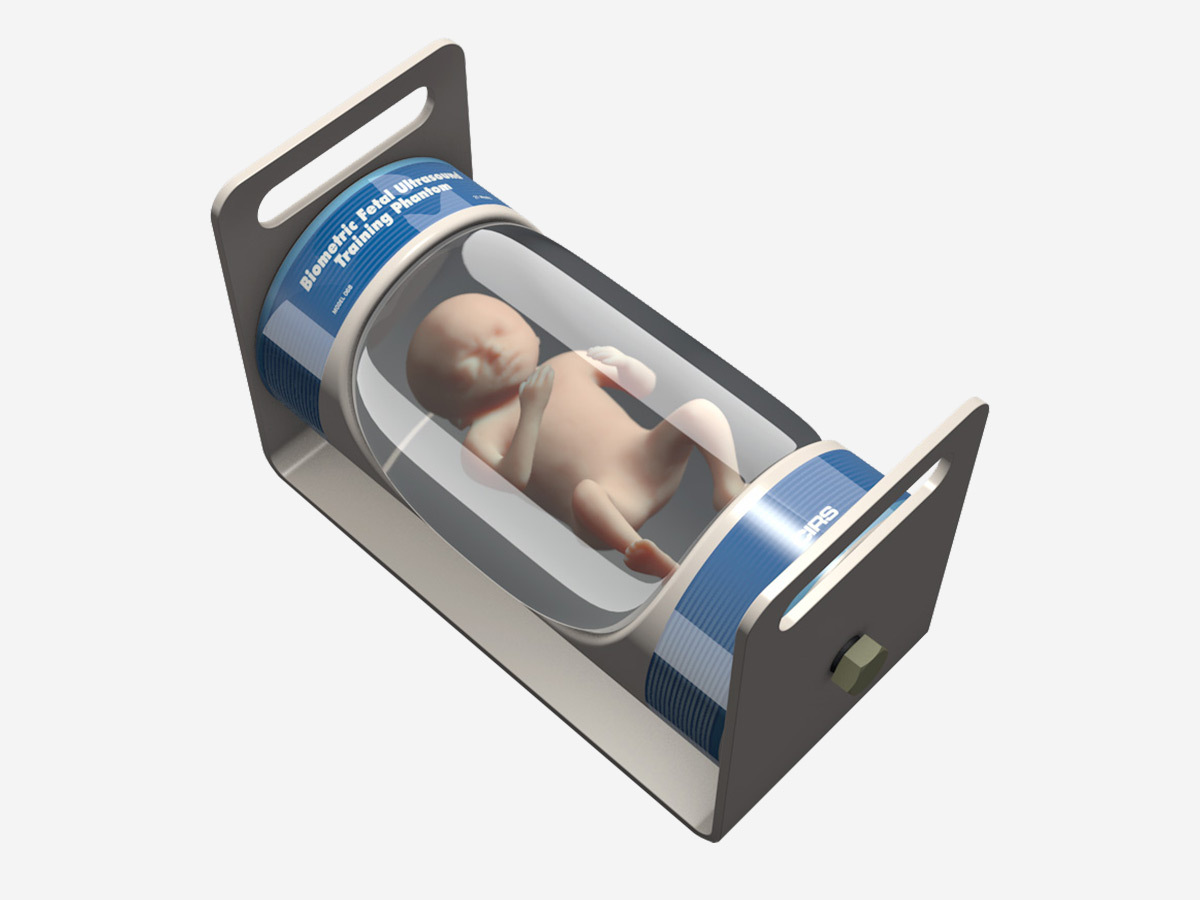

Fetal Ultrasound Biometrics Phantom

- Demonstrate system capabilities

- Teach imaging protocols to estimate gestational age

- Practice 2D, 3D & 4D fetal scan techniques

- Measure CRL, BPD, FL and AC

- Fetal Ultrasound Biometrics Phantom Datasheet

Dimension |

35 cm x 17 cm x 17 cm |

Weight |

8.9 kg (24 lbs.) |

Targeted Biometric Dimensions |

BPD: 4.2 cm (10th percentile) |

Materials |

Housing: PVC, Vinyl & ABS |